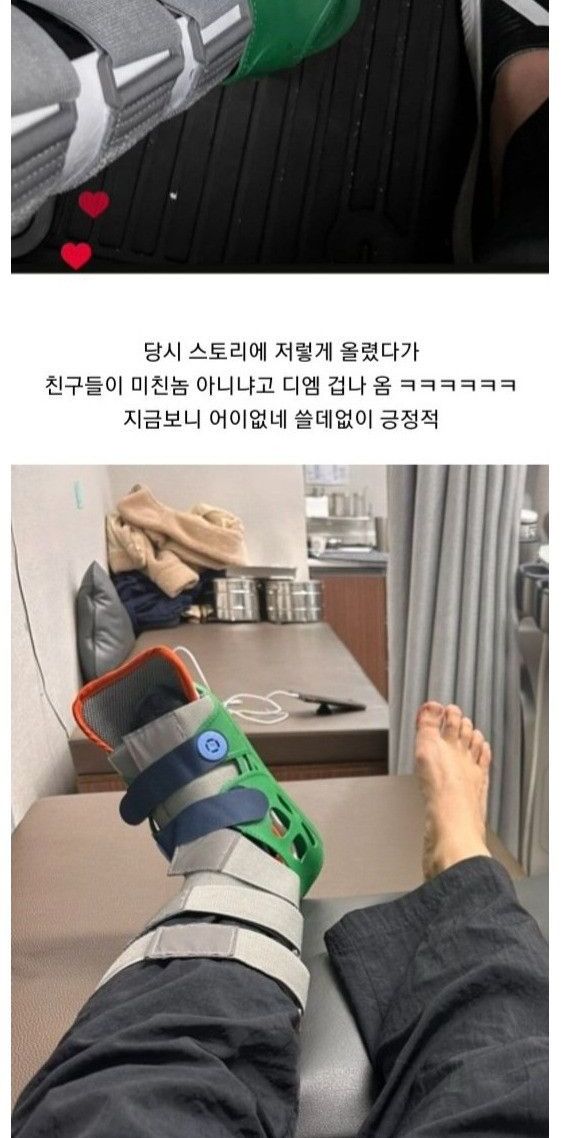

빙판길에서 자빠져 발목 부러져서 수술

한달 뒤 멀쩡하게 걸어다녀서 나중에 의사가 보고 화들짝

병원직원들한테 박수받음